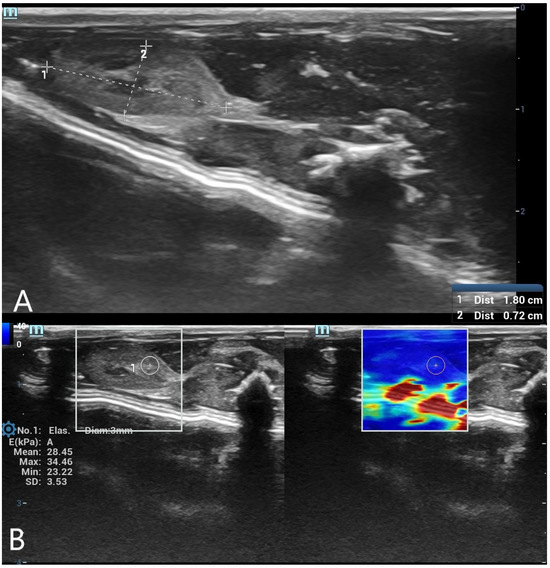

SWE measurements were acquired by a radiologist with over 8 years of experience in ultrasonography. A circular region of interest (ROI) with a diameter of 5 mm was placed centrally within the liver parenchyma, and a 3 mm ROI was used for the spleen parenchyma. ROIs were placed carefully in homogeneous tissue areas, avoiding visible ducts, vessels, or peripheral artifacts. The measurement protocol was standardized based on consensus among three radiologists before the study began. At each time point, three separate measurements were obtained and averaged. Only SWE maps without significant artifacts were included in the analysis. SWE results were recorded in kilopascals (kPa), and minimum, maximum, mean, and standard deviation (SD) values were calculated for each organ (Figure 1 and Figure 2).

Figure 2. (A) B-mode ultrasound measurement of spleen long and short diameters. A grayscale ultrasound image illustrating the measurement of spleen long and short diameters using electronic calipers. These dimensions were used to evaluate postmortem organ changes. (B) Shear wave elastography (SWE) measurement of spleen stiffness with a 3 mm region of interest (ROI). The left panel presents the grayscale ultrasound image of the spleen, while the right panel contains the SWE color-coded stiffness map. A 3 mm circular ROI is positioned within the spleen tissue to assess postmortem stiffness changes.